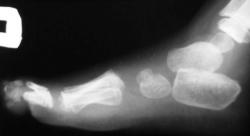

В прошлом году нашёл... Молодая девушка, у которой дополнительная 1-2 плюсневая кость с обеих сторон привела к поперечному плоскостопию и hallux valgus.

Закон парных случаев - то же у 40-летнего чабана.